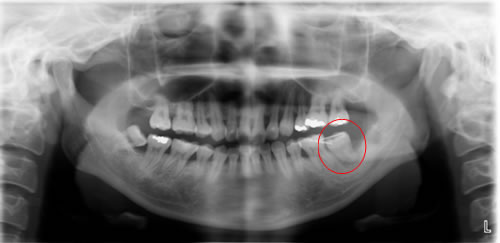

![]() |

|

移植後 |